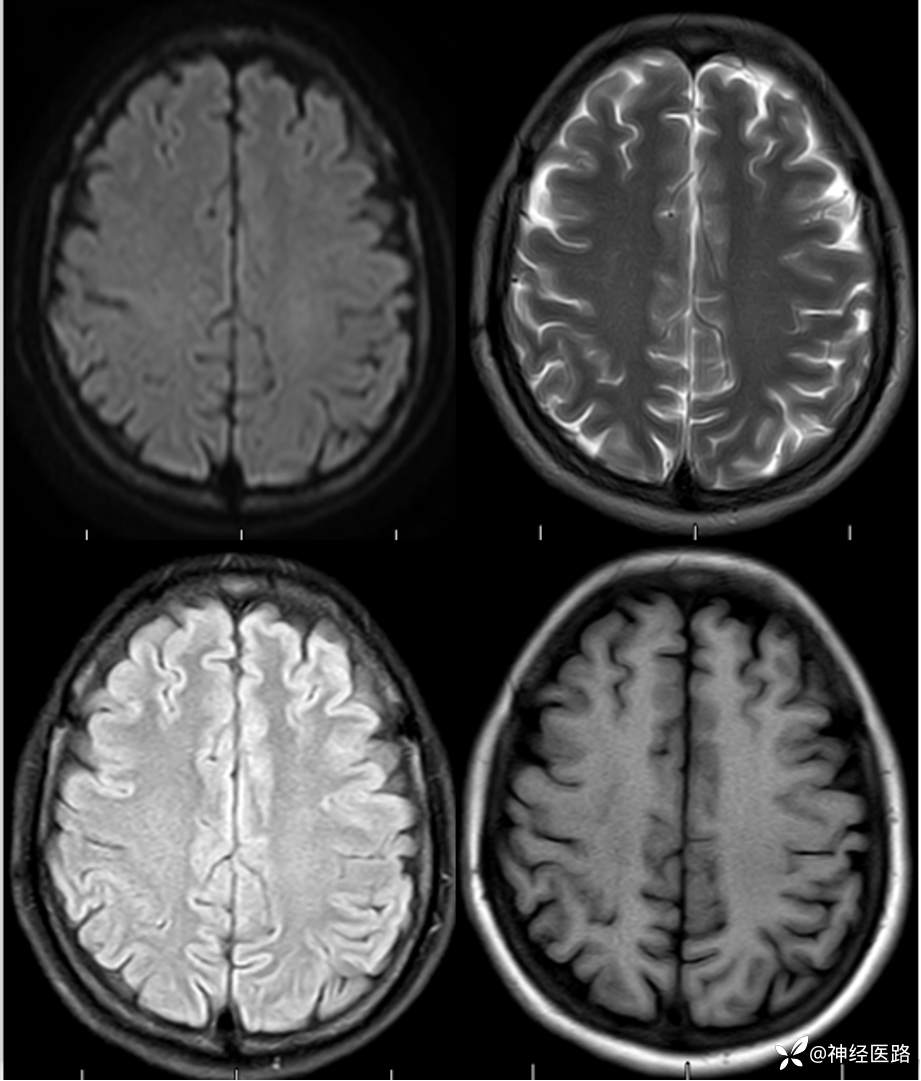

辅助检查:头部磁共振: 1.左侧额叶及右侧顶叶白质内高信号,请结合临床及相关检查。2.双侧小脑半球脑萎缩。3.部分颅骨信号增高。